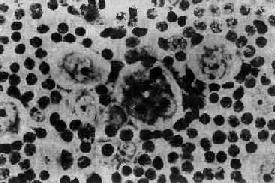

(2)HTLV-Ⅰ(人類T細胞淋巴瘤/白血病病毒):1980年美國和日本學者分離到一種病毒與成人T細胞性淋巴瘤/白血病密切相關,即HTLV-Ⅰ;雖然大部分胃黏膜相關淋巴樣組織(MALT)淋巴瘤由幽門螺鏇桿菌(Hp)引起,但是HTLV-Ⅰ感染也可導致MALT淋巴瘤。一般認為病毒感染引起腫瘤的可能途徑有2條:病毒直接誘發淋巴細胞轉化;已有異常的淋巴細胞易受病毒感染,並在此基礎上進一步轉化。